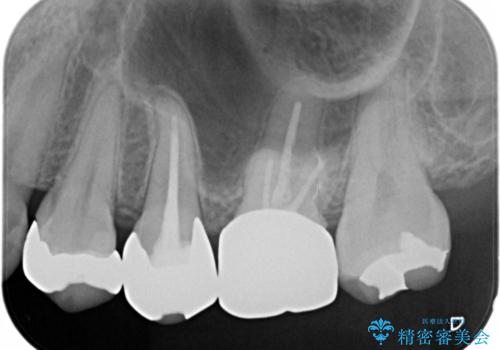

- 笑うと銀歯が目立って気になると来院された方です。まずは外から見えやすいところから治療を開始しました。

- セラミックインレー7万円・仮歯1万円・フルジルコニアクラウン7万円(精密根管治療は別途)費用は治療当時の料金となります

根管治療をした歯は神経のある歯と比較して強度が下がり、長期的に破折のリスクが高まると言われています。破折のリスクを軽減させるため、根管治療を行った歯に対しては歯冠をすべて覆うクラウンという被せ物にて補綴処置を行います。

適合不良の補綴物は二次的な虫歯発生のリスクが高まります。

自費診療で用いられる材料は保険適応の材料に比べて、より精密で適合の良い被せ物作ることができるため、長期的な虫歯のリスクを大幅に減らすことが可能です。